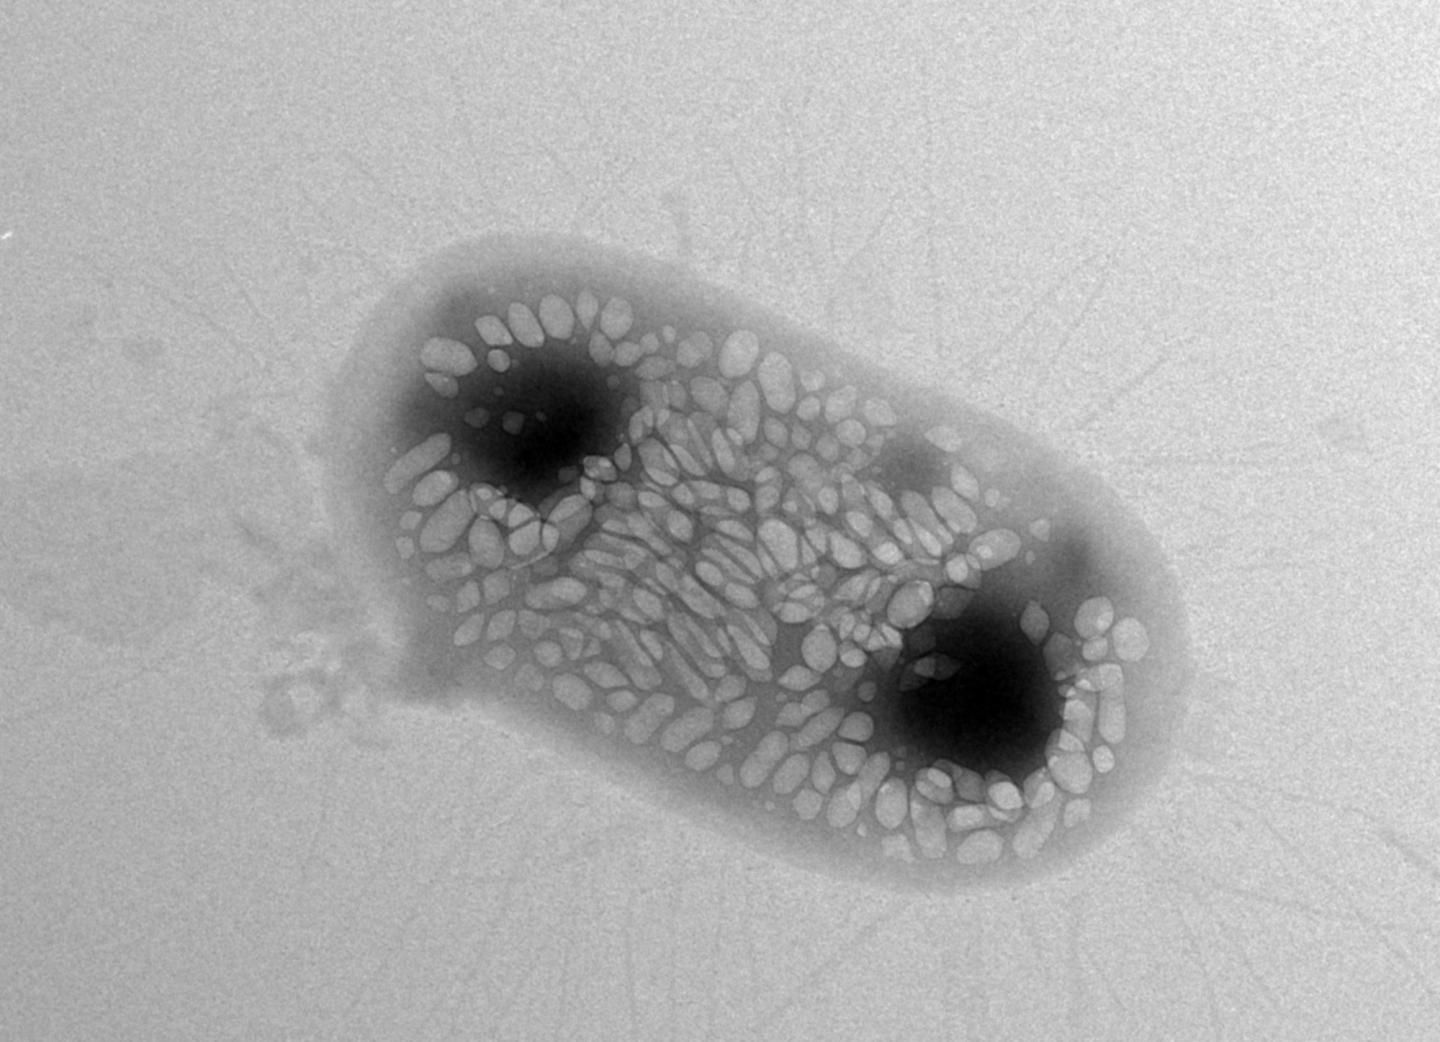

Acoustic reporter genes are genetic constructs that can be inserted into bacteria to direct them to make gas-filled nanostructures called gas vesicles. These gas vesicles can scatter sound waves, making them detectable with ultrasound. Several genes are known to encode the gas-filled vesicles, which normally help water-dwelling bacteria regulate buoyancy.

The researchers took gas-vesicle producing genes from water-dwelling bacteria and inserted them into bacteria known to colonize the gut. E. coli has been used as a probiotic to treat some gut infections. The team found a combination of genes that could make E. coli bacteria produce gas vesicles on their own. This combination of acoustic reporter genes resulted in gas-filled vesicles with the properties required for ultrasound tracking.